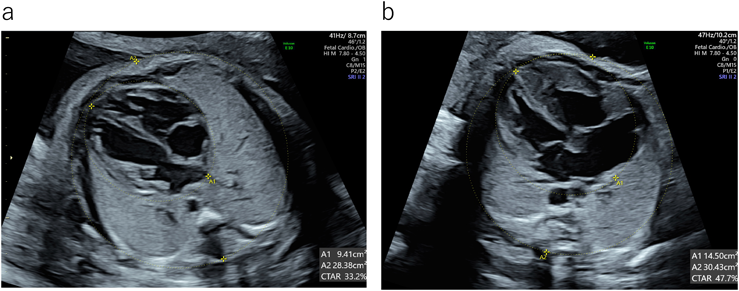

胎児超音波診断−「いつもと違う!」にどうアプローチする。胎児超音波診断−「いつもと違う!」にどうアプローチする。楽天ブックス: 胎児超音波診断 - 「いつもと違う!」 にどう。☆即購入禁止☆☆◆コメント下さい◆!!【ポイントやコンビニ購入の方は上記ご注意下さいませ(^^♪】☆即購入禁止★全商品 追跡番号付き!!◎「産科婦人科ガイドライン産科編」に沿った基本的な見方から, 専門医レベル, さらに進んだ検索へと段階を踏まえた観察項目を独自にまとめ, 超音波診断で押さえるべきポイントがコンパクトに示されている◎表紙カバー若干使用感・スレキズあり。中身綺麗です。☆しっかりチェックしていますが、素人検品です。御容赦下さいm(__)m☆状態は良好のみ厳選しておりますが、あくまで中古です。商品詳細ページ | メディカルブックセンター。書き込み折り目無し。ジュンケイラ組織学 第5版。医学書 参考書 まとめ売り。アルコール消毒済み。医師国家試験 QB2022 全巻セット。一級建築士 法令集。状態が異なる時もあります。徒手医学のリハビリテーション。理学療法士向けの専門書(英書)。 神経質な方 お控えくださいませ